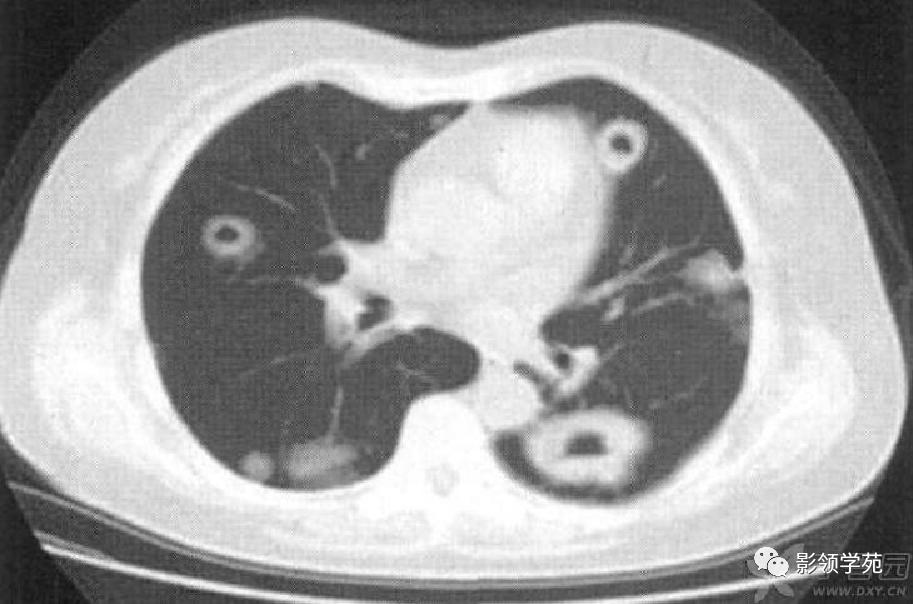

病例1:双肺多发大小不等结节,右肺中叶结节周围见晕轮征及供养血管征。

病例2:右肺下叶肿块周围见晕轮征